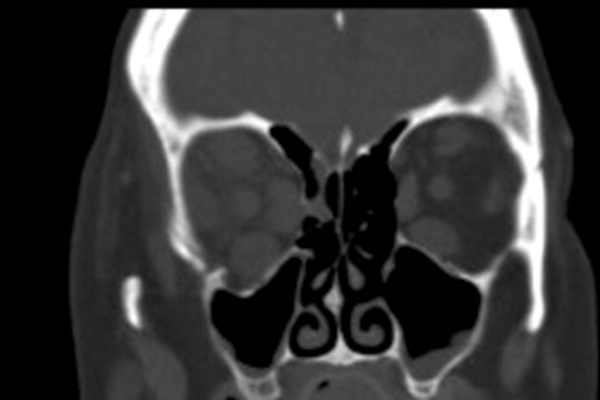

Unilateral Single Wall Decompression of Thyroid Proptosis Following an Incidental Traumatic Injury